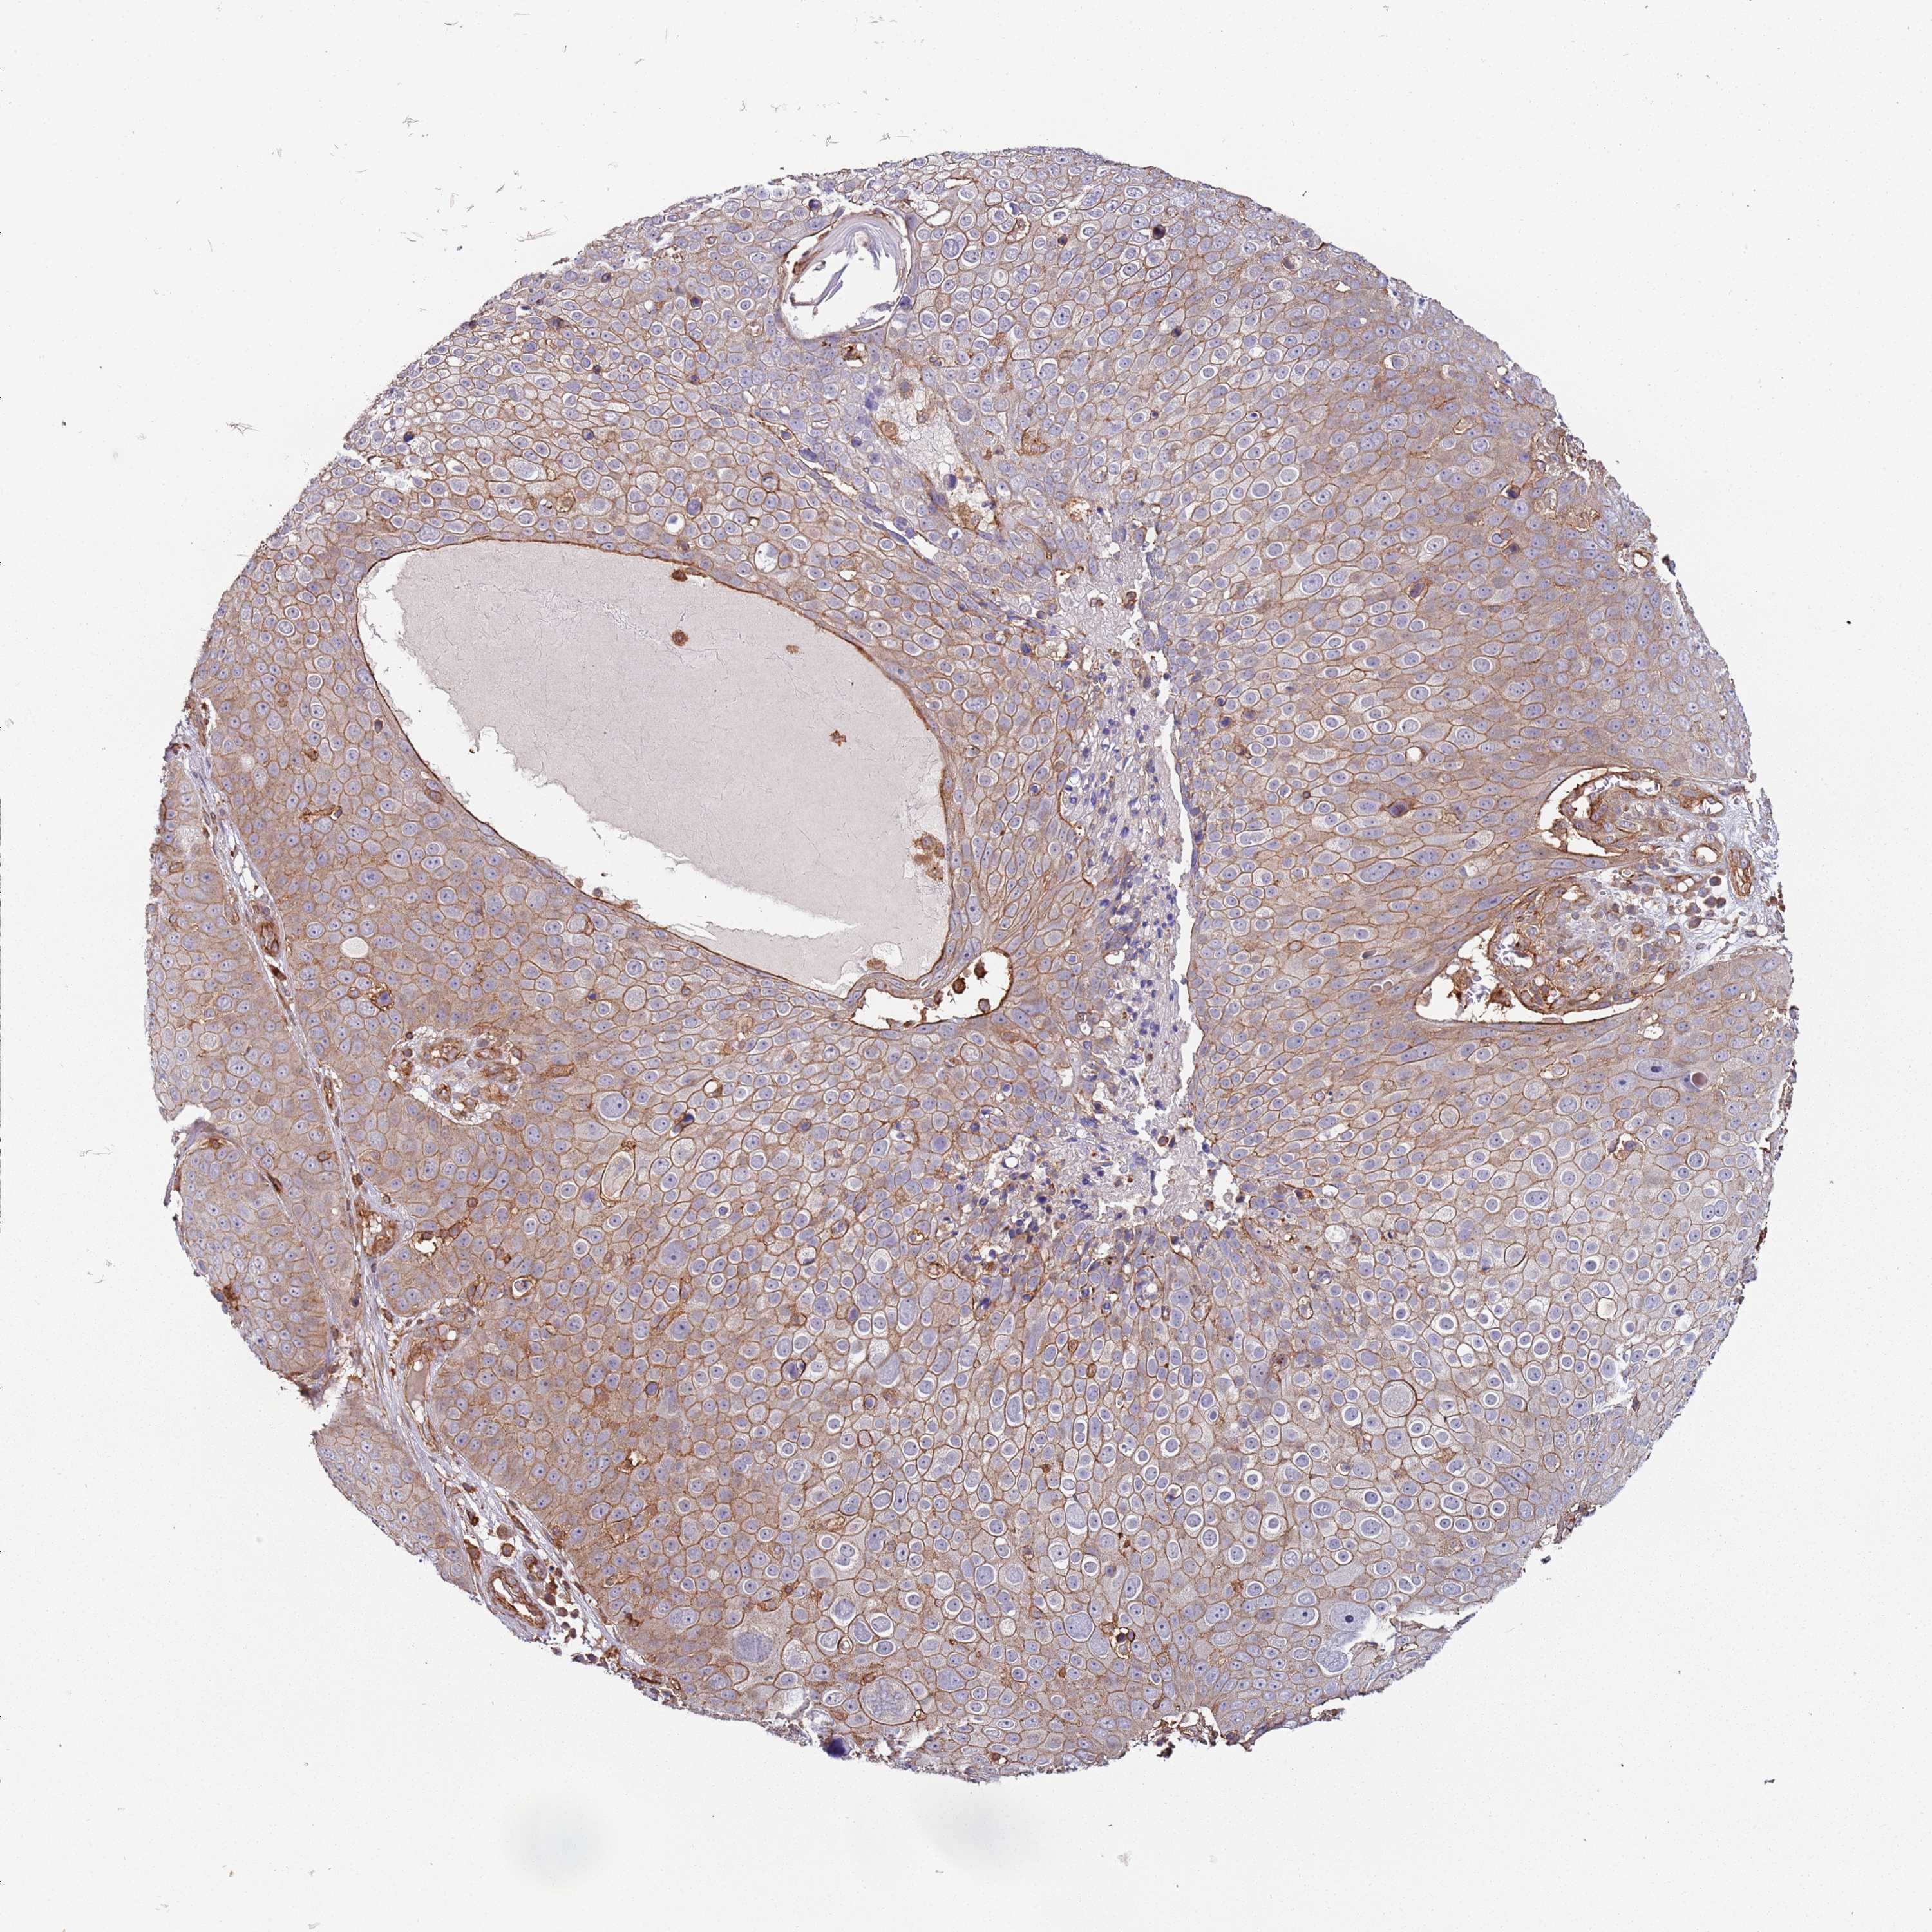

CANCER SKIN CANCER Show tissue menu

Basal cell and squamous cell cancer

SKIN CANCER - Protein expressioni

A mouse-over function shows sample information and annotation data. Click on an image to view it in a full screen mode. Samples can be filtered based on level of antibody staining by selecting one or several of the following categories: high, medium, low and not detected. The assay and annotation is described here.

Each image is clickable and will lead to virtual microscopy that enables deeper exploration of all samples and also displays staining intensity scores, fraction scores and subcellular localization as well as patient and tissue information for each sample.

Antibody HPA041622

Basal cell carcinoma